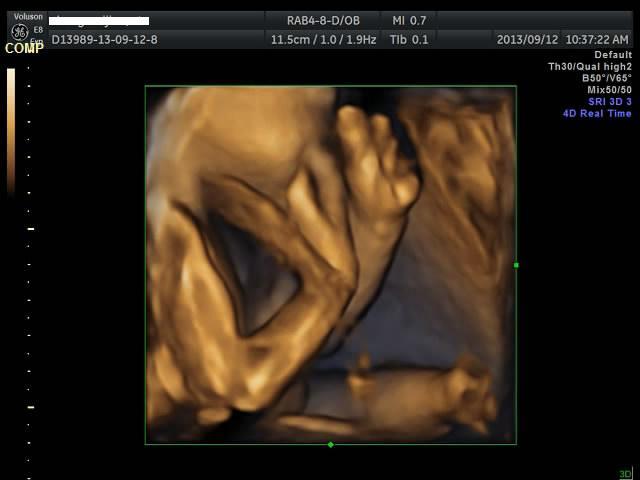

有没有能够帮我看看是千金还是帅哥的朋友?只是好奇是应该准备蓝色衣服还是应该买粉色衣服呢? 点击展开 匿名用户 2013-09-12 20:44 为您推荐: 其他回答 吓死我了... 匿名用户 2013-09-12 20:57 看不出来啊,买米黄色的吧 不论男女,都很好看 匿名用户 2013-09-12 20:57 帅哥的朋友吧,最好选粉红色的 匿名用户 2013-09-12 20:53 要怎么看才好 匿名用户 2013-09-12 20:48 千金,买粉红的 匿名用户 2013-09-12 20:47 相关问题 谁帮我看看是千金还是帅哥! 来看看我家24天的小帅哥,穿粉色衣服么么哒 张凡帅吗?很好奇听说是个帅哥,求解!!!!!!!